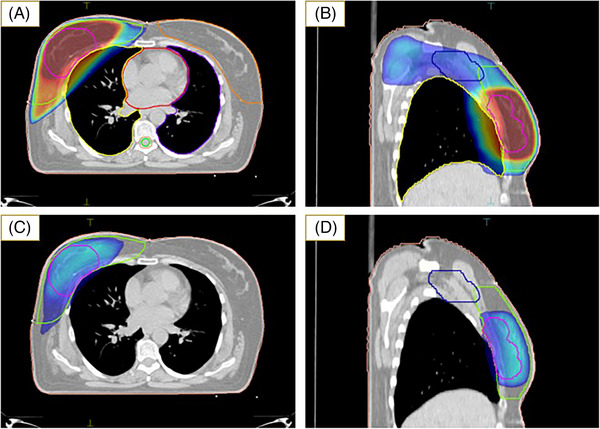

Methods: Thirty patients who underwent breast cancer surgery (BCS) with axillary lymph node dissection (ALND) were enrolled. Two plans were generated for each case: (1) dpSIB-VMAT, and (2) 3D-CRT-seqB plans. Planning target volume (PTV)-Breast and PTV-Nodes were prescribed at a dose of 50 Gy in 25 fractions in both plans. PTV-Boost was prescribed at a dose of 60 Gy in 25 fractions simultaneously in the dpSIB-VMAT plans, whereas it was planned sequentially in the 3D-CRT-seqB plans at 10 Gy in 5 fractions. Dosimetric parameters were compared between the two plans.

Abstract Image